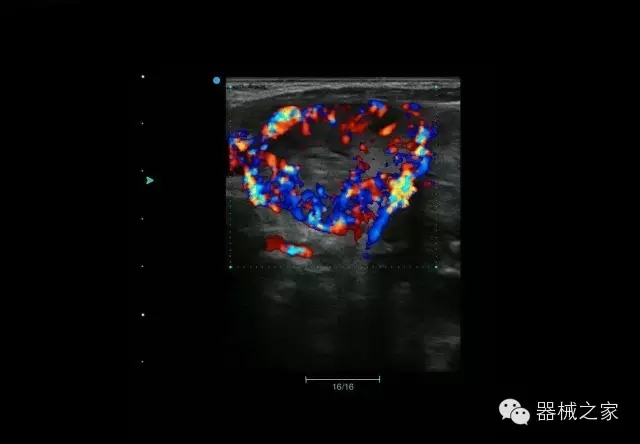

經(jīng)典產(chǎn)品:Apogee 1000

臨床圖片賞析

結(jié)甲

腎臟血流

肝血管瘤

產(chǎn)品特點

·屏幕可左右90度旋轉(zhuǎn);

·雙模操控;

·兩用提手;

·雙鋰電池;

·超輕機身;

·15寸高亮高清醫(yī)學(xué)顯示器;

·衛(wèi)星布局操控面板;

·一體化剪切板;

·多功能導(dǎo)航鍵;

“宏云”平臺

·采用移植自高端臺式彩超的“宏云”平臺技術(shù),使系統(tǒng)具有更優(yōu)秀的圖像效果;

人性化的設(shè)計

·內(nèi)置電池,輕巧的外觀設(shè)計以及臨床功能、軟硬件設(shè)計的人性化設(shè)計,使系統(tǒng)在臨床多科室移動診查中,均從容應(yīng)對;

Fusion THI二代融合諧波成像

·在不同諧波頻率段獲得的信息進(jìn)行實時融合,既能獲得諧波圖像分辨率又能提高圖像的穿透力,降低圖像噪音;

XBeam多域復(fù)合成像

·通過頻域和空域角度進(jìn)行復(fù)合的圖像處理,能有效消除由于圖像離散化和圖像衰減引起的空間分辨率下降的不利影響,彌補原有圖像空間分辨率的不足,獲得更加清晰的圖像;

CFDA注冊證編號

·粵食藥監(jiān)械(準(zhǔn))字2014第2231316號